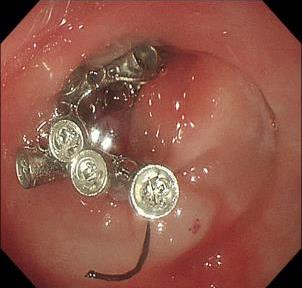

• 可旋转重复开闭软组织夹联合外科尼龙缝合线法闭合结直肠内镜黏膜下剥离术后缺损的临床应用价值

2025, 31(12):77-82. DOI: 10.12235/E20250091

摘要 (77) HTML (65) PDF 1.86 M (64) 评论 (0) 收藏

摘要:目的 探讨可旋转重复开闭软组织夹联合外科尼龙缝合线法(ROLM)闭合结直肠内镜黏膜下剥离术(ESD)后黏膜缺损的临床疗效。方法 回顾性分析2024年1月-2024年6月15例在南京医科大学附属常州市第二人民医院因早期结直肠肿瘤行ESD,并采用ROLM闭合黏膜缺损患者的临床资料。观察患者病灶相关情况(病灶部位、缺损最大径和术后病理)、手术相关情况(术后缺损成功闭合率、钛夹使用数量、ROLM缝合时间和住院时间)、术后并发症发生情况和术后随访情况。结果 术后缺损成功闭合率为100%。病灶长径3.0~6.0 cm,平均(3.7±0.8)cm。缺损部位:回盲部1例,升结肠6例,横结肠肝曲1例,降结肠2例,乙状结肠3例,直肠2例。术后病理为:管状腺瘤8例,黏膜下囊肿1例,管状绒毛状腺瘤5例,胃肠道间质瘤1例。钛夹使用数量为7~20枚,中位数为11(10,13)枚。ROLM缝合时间为13~37 min,平均(19.3±6.5)min。住院时间4~9 d,平均(6.5±1.2)d。术后无出血、穿孔、感染和消化道狭窄等并发症发生。术后3~6个月复查肠镜,手术创面均愈合良好。结论 ROLM能够安全、有效地闭合结直肠ESD后黏膜缺损。值得临床推广应用。